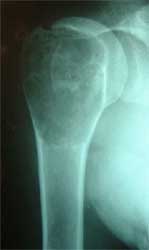

肱骨近端软骨肉瘤,肿瘤段截,用13厘米长的异体骨,

修复肱骨近段,人工肱骨头置换术后3年